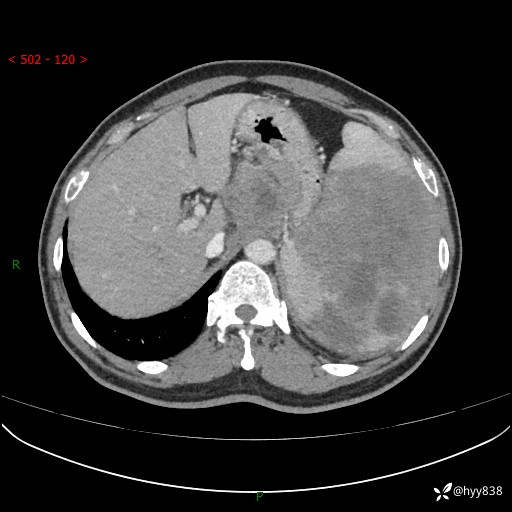

上腹部CT平扫

增强(动脉期+静脉期)